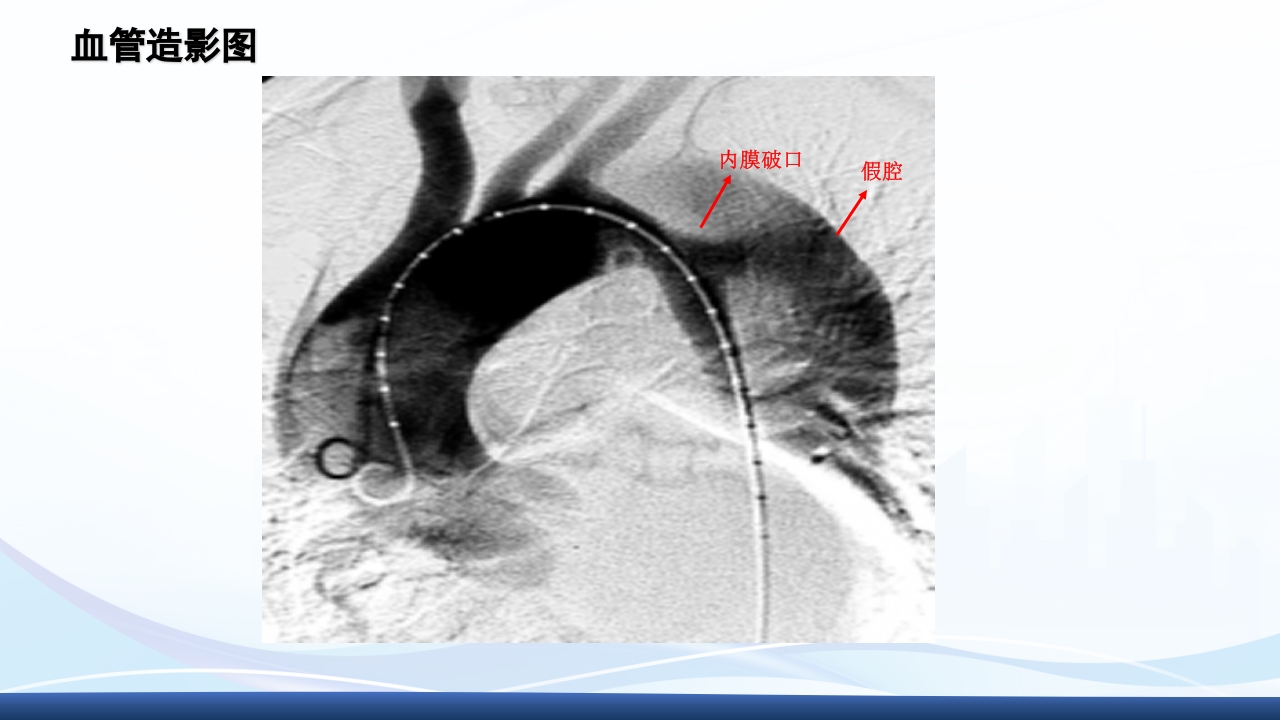

大纲 1 主动脉夹层的概念 2 病因与发病机制、分型 3 临床表现3 、辅助检查 4 主动脉夹层的诊断、治疗 5 病例介绍 64 护理诊断与措施、健康宣教 解剖图 解剖图 主动脉夹层的概述 主动脉夹层(aortic dissection AD)指主动脉壁中层 撕裂、分离,使主动脉壁内形成血肿,并沿纵向延伸。 AD最常发生在50-70岁的男性,男女性别比约2-5:1, 是与人类主动脉有关的最常见的死亡原因。 Thoraci caorta Abdomin alaorta Aortic dissection Aorta Blood in wall of artery Blood in artery 病因 结缔组织遗传缺陷性疾病:如马方(Marfan)综合征、埃-当(Ehlers-Danlos)综 合征、先天性主动脉缩窄、二叶主动脉瓣及二尖瓣脱垂等患者。 高血压:临床与动物实验发现,不是血压的高度...